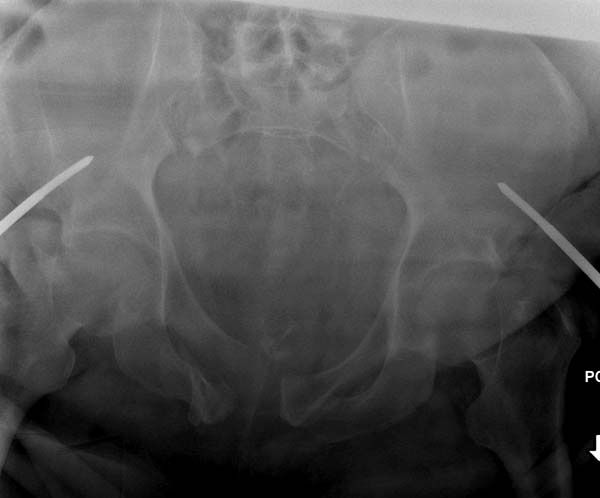

Вход в таз

Добрый день! Коллеги. Согласно классификации АО диагноз по рентогенограммам следует кодировать следующим образом 61-С2.2 а1)в1)с8),иначе говоря: полный унилатеральный разрыв заднего полукольца слева через крестцовоподвздошное сочленение (скорее всего с переломом задних отделов подвздошной кости), неполный разрыв заднего полукольца справа (по типу "открытой книги"), разрыв лонного сочленения в сочетании с переломом лонной и седалищной костей справа. Однако, есть ряд других моментов которые следует учесть при постановке диагноза и выборе тактики лечения.

“При поступлении обследована (обзорный таза + вход в таз)”